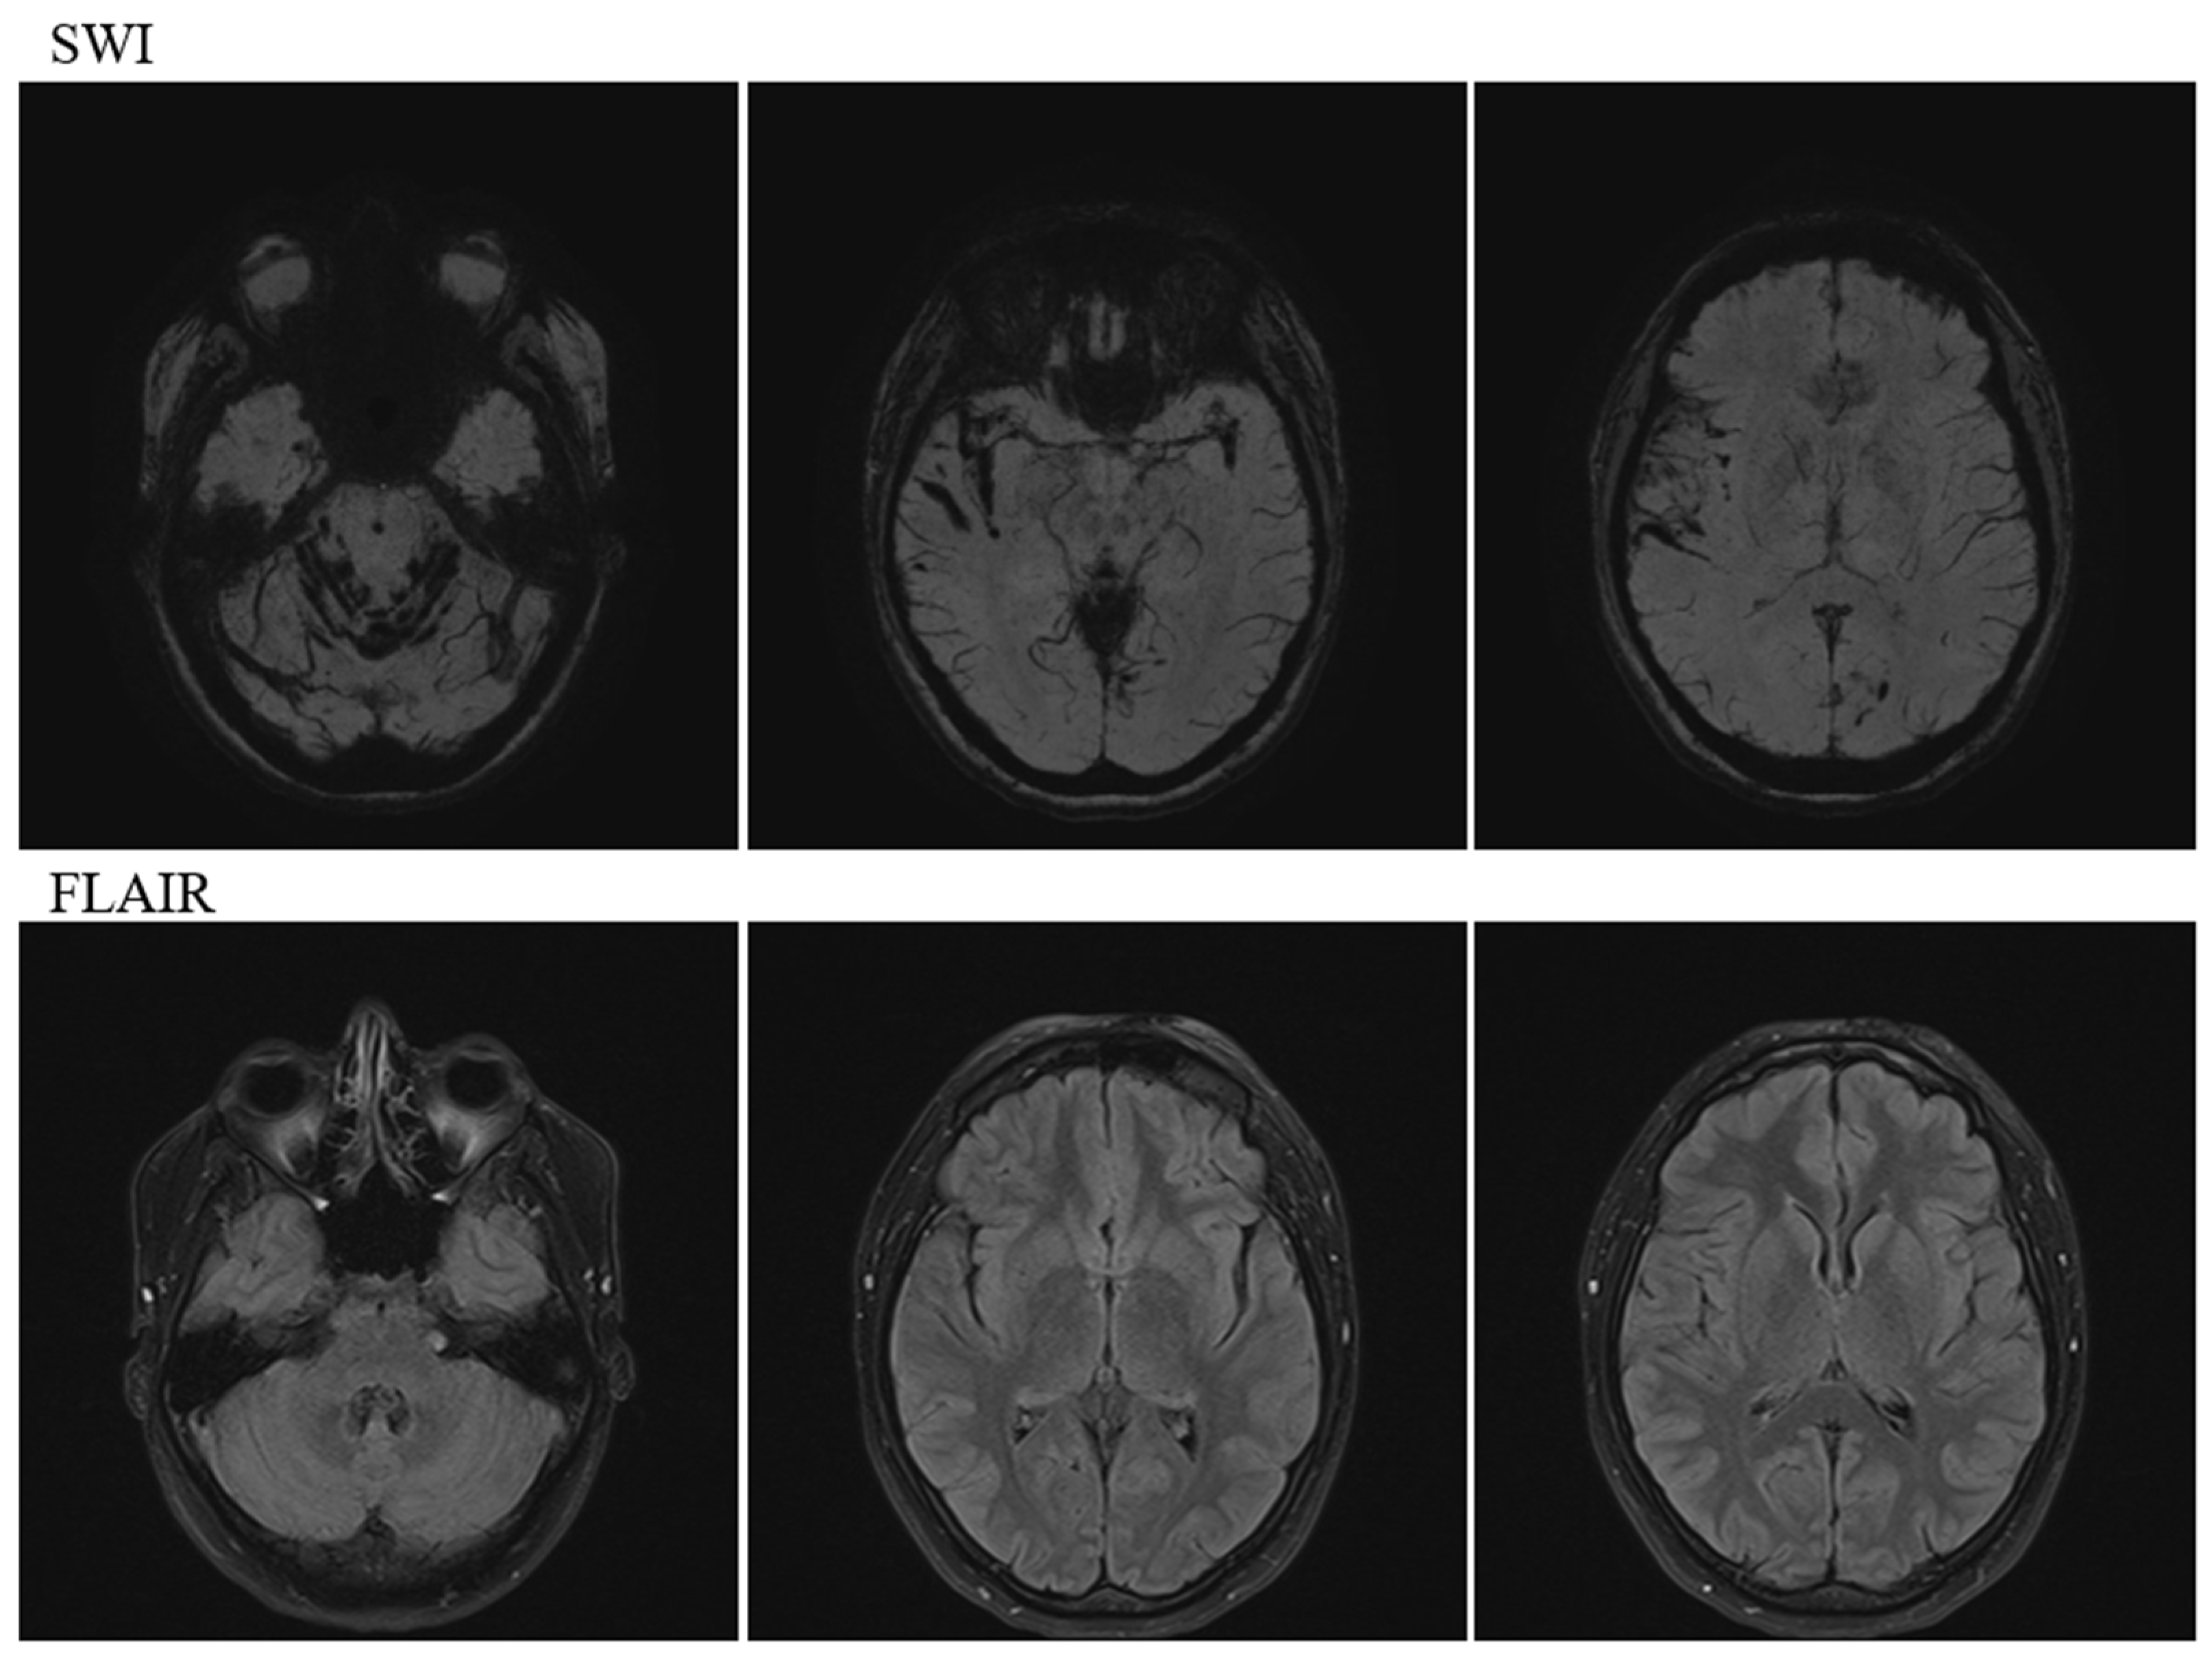

A Case of Idiopathic Intracranial Hypertension Complicated with both Infratentorial and Supratentorial Cortical Superficial Siderosis: Novel Imaging Findings on Intravoxel Incoherent Motion Magnetic Resonance Imaging Offering Clues to Pathophysiology

2. Case Description